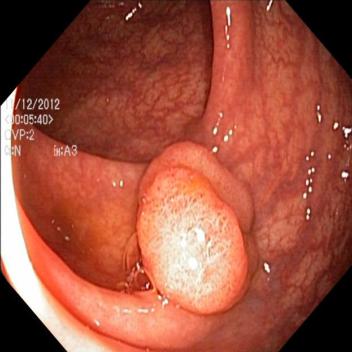

(a) Original Image

(b) GT

(c) Augmented Image

(d) Augmented GT

The pasting module and the update module of the potential map are implemented iteratively 10 times. Thus the foreground area may appear in multiple locations, and an example is depicted in Fig 1.